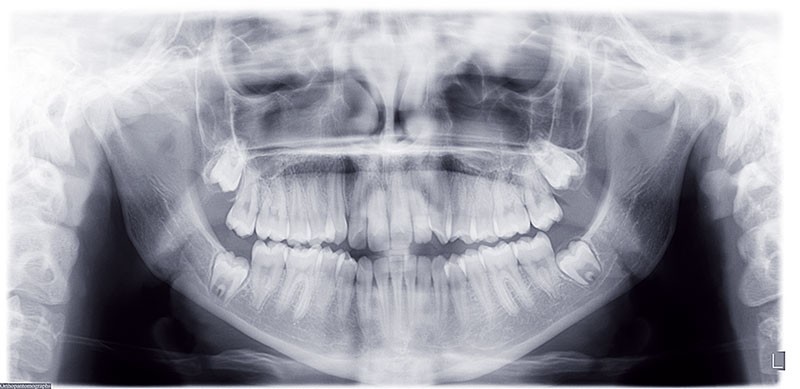

Nous sommes en présence d’une patiente en fin de croissance faciale, âgée de 16 ans. Elle présente une classe III dentaire et squelettique associée à une asymétrie faciale de type latérognathie mandibulaire avec déviation des points interincisifs et déviation du menton vers la gauche.

Pour des raisons personnelles, la patiente refuse un protocole orthodontico-chirurgical. Nous optons pour une réduction de la classe III par compensations dento-alvéolaires car la progénie n’est pas très importante et nous estimons que le résultat dentaire, squelettique et facial peut être cohérent. Un système « Motion Classe III Carriere » va être utilisé suivi d’un appareillage multibague « Carriere SLX ».